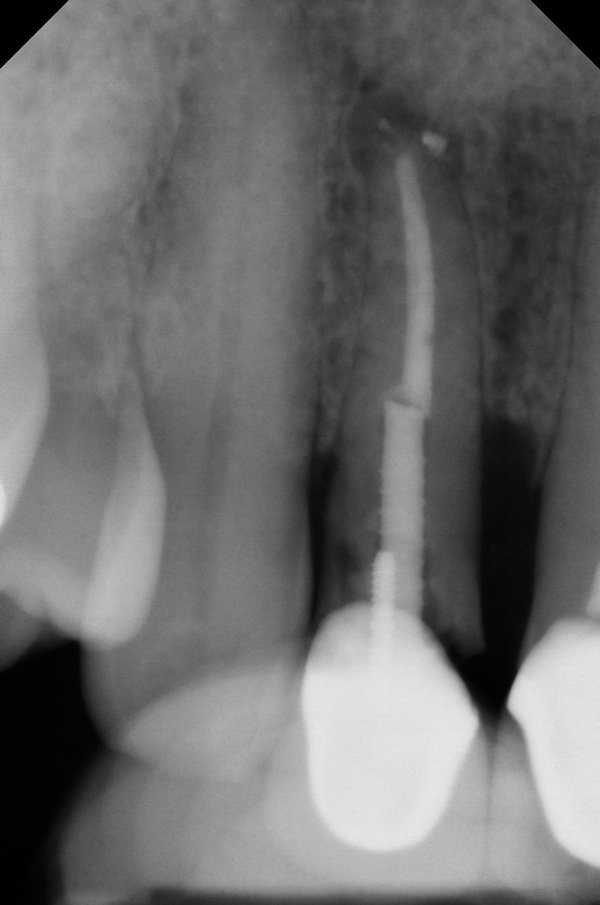

A minimum of 2 mm of facial bone thickness has been proposed as the “critical bone thickness” for the prevention of vertical height loss of the facial plate. It has been reported that when the distance of the buccal shoulder position of the implant to facial bone plate is below this critical thickness, an increased amount of facial bone resorption may be observed, which, in turn, may increase the chance of implant mucosal recession and failure (Figure 1). When the facial bone thickness is more than 2 mm from the implant buccal shoulder position, the likelihood of facial bone loss is decreased and the chance for alveolar bone stability is, therefore, increased.16

Chen and coworkers evaluated the soft-tissue and radiographic outcomes of implants placed in extraction sockets using a nonsubmerged protocol. The result showed statistically significantly higher marginal tissue recession at sites when implants were placed 1.1 mm from the inner buccal socket wall compared with implants placed 2.3 mm from the inner buccal socket wall. Six of the eight implant cases that were buccally positioned had unsatisfactory post-restorative esthetic outcomes. The authors concluded that position of the implant shoulder within the socket is a critical factor for ideal esthetic outcomes; thus, a minimum of 2 mm distance from the implant shoulder to the inner buccal shoulder wall was recommended to prevent implant marginal tissue recession.5